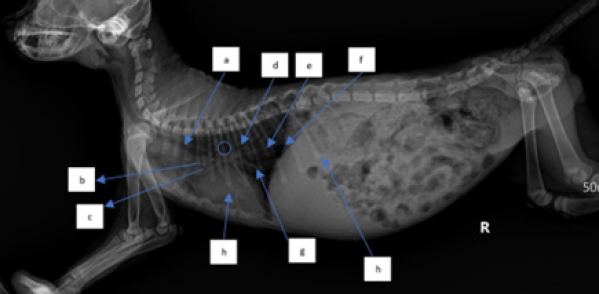

In examining the size of the heart via dorsoventral X-ray, the method used is a comparison of the width of the heart and the width between the right and left ribs and the comparison of the length of the boundaries of the right and left ribs with the heart. The measurement results in (Fig. 6) show a comparison of the length of the border of the right and left ribs with the heart RL, the length of the border between the ribs and the heart on the dexter and sinister parts is not the same (abnormal). In measuring the comparison of the width of the heart and the width between the right and left ribs, length B is greater than 2/3 A (abnormal), whereas normal is BA (Holland, 2020).

When evaluating the cardiac dimensions through dorsoventral X-ray analysis (Birsan et al., 2017), a technique employed involves assessing the heart’s width relative to the space between the right and left ribs, as well as comparing the length of the right and left rib margins concerning the heart. The findings in Figure 6 indicate a comparison between the length of the border of the right and left ribs against the heart RL. Notably, there exists an abnormality in the length of the border between the ribs and the heart on the dexter and sinister parts, as they are not of equal dimensions. According to Holland (2020) findings, aberrant results were obtained when assessing the ratio of the width of the heart to the width between the right and left ribs, with length B being greater than 2/3 A. In contrast, a normal outcome was observed when the ratio of B to A was within typical parameters.

Fig. 2. Thoracic radiograph of Hiro’s cat in a dorso ventral (DV) changes in vascular patterns with dilatation of the pulmonary arteries and veins caudals.

Fig. 3. Thoracic radiograph of Hiro’s cat in a lateral position with a dilated heart with an enlarged heart size. (a). Trachea, (b). cranial pulmonary artery, (c). pulmonary vein, (d). aorta, (e). pulmonary caudalis arteries and veins, (f). diaphragm, (g). vena cava caudalis, and (h). ascitic fluid.

The way to measure the heart with the vertebrae heart size (VHS) method is by measuring it by drawing straight lines on the short axis and long axis (James, 2000), then the measurement results are aligned with the vertebrae and starting from the 4th rib (Marbella et al., 2023) then add up by looking at how long the vertebrae are. The normal size of VHS in the Buchanan and Bucheler method is 7.5 vertebrae (VT). In the case of Hiro’s cat (Fig. 6). VHS size using the Buchanan and Bucheler method (Litster and Buchanan, 2000) is 8 vertebrae with a long axis of 4.5 VT and a short axis of 3.5 VT so that the total becomes 8 VT (larger than normal size).

During the X-ray examination, heart measurements were taken to identify any changes in the size of the heart organ. The lateral view measurements resulted in an intercostal measurement technique score of 4, with a normal range of 2.3–3.5. The height from the apex to the vertebral column was also measured compared to the carina, resulting in A being greater than 1/3 A + B and B being greater than 2/3 A + B (normal values are A < 1/3 A + B and B < 2/3 A + B). The VHS was also measured, and there was an increase in VHS results in CHF cases as mentioned in previous research in cats (Smith et al., 2004; antecedent corticosteroid administration has been noted in cats with congestive heart failure (CHFLaudhittirut et al., 2020), resulting in a score of 8 VT (the normal value is 7.5 VT). Measurements were then taken using the dorsoventral position, resulting in the heart size being different in R and L distances, with L being larger than R. The size of B was also greater than 2/3 (normally, R is equal to L, and B is less than 2/3). From these measurements, it was determined that the heart was enlarged or experiencing cardiomegaly. Cardiomegaly is the heart’s compensation for heart failure to meet the body’s circulatory needs, which can be caused by congestive heart failure (CHF), valvular heart disease, and cardiomyopathy (Triakoso, 2020).

Following changes occur in the caudal pulmonary arteries and veins or vascular patterns observed in the dorsoventral view of the X-ray position, specifically alterations in size. The pulmonary veins and arteries caudalis exhibit dilation, resulting in a vessel diameter larger than the IXth rib diameter, this is consistent with previous research, which states that enlargement of the left atrium and pulmonary veins is one of the symptoms of CHF in cats (Guglielmini and Diana, 2015; Bernes et al., 2020). The dilation of pulmonary arteries and veins is due to augmented pressure from systemic veins toward the right ventricle (Berry, 2010). The upsurge of pressure from systemic veins toward the right ventricle is caused by the improper blood circulation process in the right atrium and ventricle, leading to a small output of blood from the ventricles and the retention of blood in the heart chambers at the end of systole, which increases. This condition increases hydrostatic pressure, leading to the dilation of pulmonary arteries and veins (Triakoso, 2020). The high hydrostatic pressure causes fluid leakage from veins into pleural and peritoneal spaces, and potentially into pericardium and peripheral interstitial tissues. Ascites occur when fluid leakage surpasses the lymphatic system’s capacity (Tilley et al., 2021).